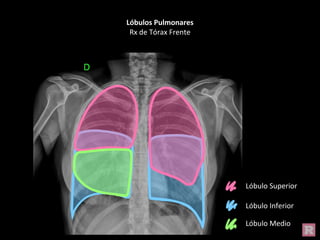

Lóbulos Pulmonares

Rx de Tórax Frente

Lóbulo Superior

Lóbulo Inferior

Lóbulo Medio